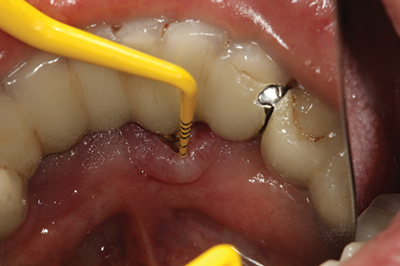

Peri-implantitis has been defined as an inflammatory process that affects the tissues around an osseointegrated implant in function and, like periodontitis, results in loss of supporting bone6 (Figs. 3 and 3a). The prevalence of peri-implantitis has been shown in some studies to range from 11% to as high as 47% of implant sites analyzed.(16) Most literature reviews agree that once bone loss has occurred around an implant, nonsurgical therapy is not as effective as surgical treatment.(17) Surgical intervention by the dentist or specialist includes raising a full thickness flap around the affected dental implant in order to completely expose the dental implant surface (Fig. 4). Mechanical debridement with hand and high-speed instrumentation as well as irrigation with various medicaments is advocated in order to detoxify the implant surface and alleviate bacterial contamination. After decontamination, the flap can be apically or coronally positioned. In addition, various regenerative technologies, including bone and soft-tissue grafts, growth factors, and barrier membranes have been used to rebuild lost tissue support around the dental implant (Figs. 5 and 5a). Different methods of guided bone regeneration around implants affected with peri-implantitis were demonstrated, and the results have been shown to be stable for a follow-up period of up to seven years.(18) That being said, no gold standard of peri-implant disease has been documented and "available evidence does not allow specific recommendations for the therapy of peri-implantitis."(19)